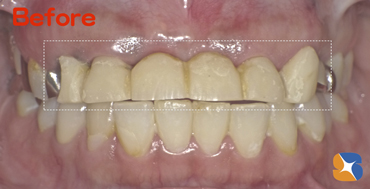

70代の女性。主訴は「前歯を2カ所、綺麗にしたい」でした。

A)詰め物の変色

B)被せ物の変色が認められました。

A),B)共にメタル不使用の白いセラミック(オールセラミック)を装着しました。 続きを読む